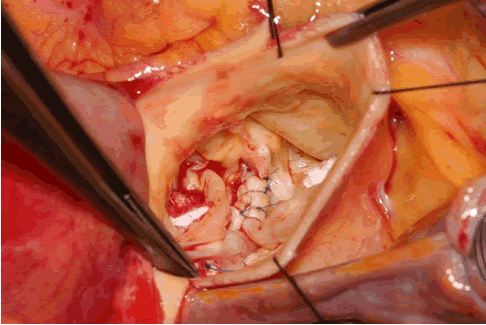

Reconstruction Of The Bicuspid Aortic Valve - Optechtcs.com

Reconstruction of the Bicuspid Aortic Valve Hans-Joachim Schäfers, MD A bicuspid aortic valve (BAV) occurs in 2% of the popula- and avoid retraction of the cusp (C). Even in the presence of more extensive calcification, repair is possible. ... View This Document

Tricuspidization Of Incompetent bicuspid aortic valve

Tricuspidization of incompetent bicuspid aortic valve Kohei Kawazoe, MD, Hiroshi Izumoto, MD, Jyunichi Tsuboi, Bicuspid aortic valve is one of the main causes of AR, we may be able to avoid or minimize the risk of postoperative ... Read Full Source